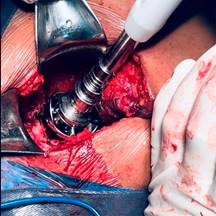

Con la paciente bajo anestesia regional y previa profilaxis antibiótica, se coloca en posición de cubito lateral derecho. Por anatomía de superficie se identifican referencias anatómicas: trocánter mayor y diáfisis femoral. Se realiza un abordaje lateral directo de Hardinge, disección por planos aplicando hemostasia con electrocauterio, se hace un corte longitudinal de fascia lata con tijera de Metzenbaum; se efectúa colgajo muscular de glúteo medio y menor (Figura 2); posterior a esto, capsulotomía en T invertida, para identificar cabeza femoral y realizar osteotomía a 10 mm por arriba del trocánter menor; se identifica ligamento redondo (Figura 3), con el fin de diseccionar hasta su origen sobre la escotadura y localizar el acetábulo nativo, retirando tejido blando remanente de cápsula articular (Figura 4).

Tiempo acetabular: se colocan separadores de Richardson en el polo superior y Hoffman sobre pared anterior del acetábulo; las características anatómicas pierden contención anterior y superior, quedando como estructura de soporte la pared y columna posterior, por lo que se realizó una osteotomía longitudinal y horizontal del borde interno de la pared posterior de aproximadamente 5-8 mm y tectum acetabular (Figura 5). Esto permite que, al efectuar el rimado acetabular, se descienda el centro de rotación, con una adecuada orientación y cobertura del componente protésico no cementado (Figura 6).